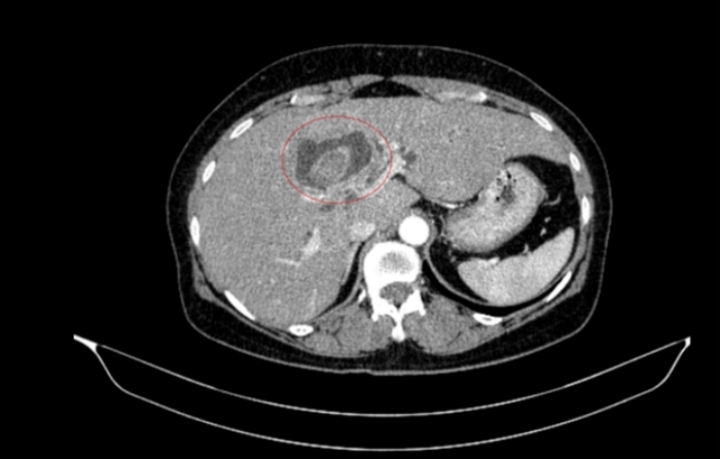

Hình ảnh sỏi đường mật tạo ổ áp xe gan - đường mật gan trái (vòng tròn màu đỏ).

Một phụ nữ 59 tuổi được các bác sĩ Trung tâm Y học hạt nhân và Ung bướu, Bệnh viện Bạch Mai, tiếp nhận trong tình trạng vàng da, ngứa và đau vùng hạ sườn phải kéo dài. Kết quả chẩn đoán hình ảnh ban đầu ghi nhận tổn thương đường mật trong gan kèm sỏi và giãn đường mật.